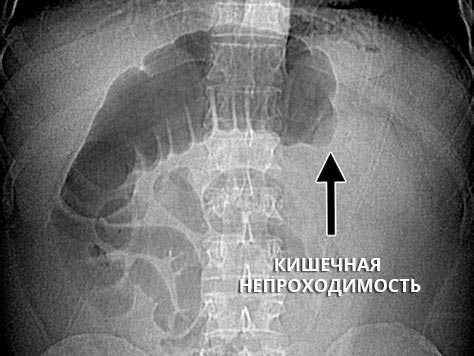

Инструментальные исследования, необходимые для определения синдрома, проведенные до госпитализации в организацию по оказанию паллиативной помощи:при острых состояниях ― простой рентгенологический снимок живота (если есть признаки кишечной непроходимости или скопление большого количества каловых масс в толстом кишечнике).

Рентгенография ОБП при кишечной непроходимости

Если у онкологического больного появились признаки кишечной непроходимости, его нужно срочно госпитализировать в стационар. Самый простой и быстрый способ диагностики кишечной непроходимости — обзорная рентгенография брюшной полости. На снимках можно увидеть раздутые газом участки кишки, скопление жидкости. Один из характерных симптомов — так называемые чаши Клойбера — скопления воздуха и жидкости, которые внешне напоминают перевернутые чаши или буквы «U». [2,12]

Наиболее простой, быстрый и доступный метод диагностики – это обзорная рентгенография органов брюшной полости. На снимках обнаруживаются характерные признаки:

- Чаша Клойбера – видны расширенные петли кишечника в виде куполов, и в них горизонтальный уровень жидкости. Эта картина напоминает перевернутую вверх дном чашу. Чаш может быть несколько, на снимке они наслаиваются друг на друга.

- Кишечные аркады – возникают из-за раздувания газами петель тонкой кишки, в нижних коленах кишки визуализируется горизонтальный уровень жидкости.

- Складки Керкинга – из-за растяжения тощей кишки на рентгенограммах она приобретает вид растянутой пружины.